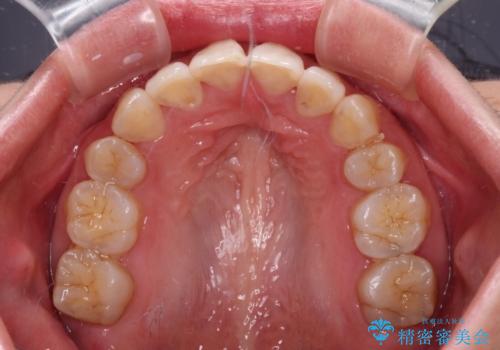

Eラインを改善したい ハーフリンガルによる抜歯矯正

- 口元の突出感を気にして来院された患者様です。

上下左右の第一小臼歯4本を抜歯して口元を下げる治療計画としました。

舌の突出癖が強く、口元を引っ込める力に拮抗してしまい、抜歯スペースを閉じるまでに時間がかかりました。

また途中出産もありましたが、無事に治療を終えることができました。